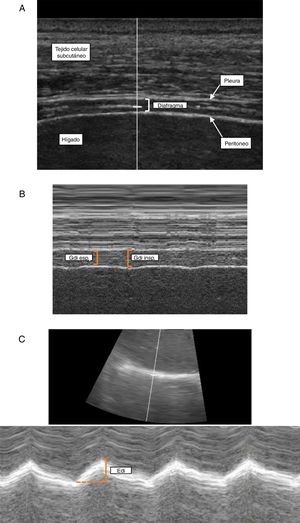

Técnica. La medición del Gdi mediante ecografía se realiza en el hemidiafragma derecho a nivel de la zona de aposición diafragmática. Esta zona corresponde al área de la pared torácica donde el contenido abdominal alcanza el sector inferior de la cavidad torácica y se topografía entre el 8° y 10° espacio intercostal, a nivel de la línea axilar media. Con el paciente en decúbito dorsal (30-45°), se emplea un transductor lineal de alta frecuencia (≥ 10MHz) colocado paralelo al espacio intercostal y perpendicular a la piel27. Se utiliza inicialmente el modo bidimensional (modo B) para obtener el mejor enfoque y seleccionar la línea de exploración (fig. 1A). En esta área el diafragma se identifica como una estructura formada por 3capas paralelas (aproximadamente a 1,5-3,0cm de profundidad): una capa central hipoecoica (el diafragma propiamente dicho) delimitada por 2capas ecorrefringentes (peritoneo y pleura parietal)44. Puede observarse además cómo el artefacto pulmonar (correspondiente al ángulo costofrénico) borra la imagen del diafragma durante la inspiración36. Manteniendo el transductor en posición, se utiliza el modo M para determinar el Gdi correspondiente a la distancia comprendida entre ambas capas ecorrefringentes, medida aproximadamente a 2cm del ángulo costofrénico (fig. 1B). Como mencionamos previamente, la medida basal del Gdi se realiza al final de la espiración pasiva. No obstante, la determinación del Gdi durante distintas etapas del ciclo respiratorio permite evaluar parámetros funcionales como la FEdi.

Ecografía diafragmática. Determinación del grosor diafragmático a nivel de la zona de aposición con la pared torácica en modo B (A) y modo M (B) y evaluación de la excursión diafragmática (C).

Edi: excursión diafragmática; Gdi esp: grosor diafragmático espiratorio; Gdi insp: grosor diafragmático inspiratorio.

Técnica. La determinación de la FEdi requiere la medida del Gdi al final de la espiración y al final de la inspiración. En términos prácticos, esto corresponde a los valores mínimo y máximo, respectivamente, durante la medición del Gdi en modo M (fig. 1 B)27,29.

Técnica. Con el paciente semisentado (30-45°) se emplea un transductor convexo (3,5-5MHz) ubicado a nivel subcostal derecho entre la línea medio clavicular y la línea axilar anterior27,48. El mismo será dirigido en sentido medial, cefálico y dorsal, de manera que el haz ultrasónico alcance perpendicularmente el tercio posterior del hemidiafragma44. Inicialmente, se emplea el modo B para obtener el mejor enfoque y seleccionar la línea de exploración. En este modo identificaremos el diafragma como una línea hiperecogénica que se relaciona directamente con el hígado por debajo y con el parénquima pulmonar por encima. Una vez identificadas las estructuras en modo B, utilizaremos la línea de exploración lo más perpendicular posible al diafragma y activaremos el modo M con el objetivo de evaluar el movimiento de las estructuras anatómicas a lo largo de la línea seleccionada (fig. 1 C). La Edi se medirá como el desplazamiento del diafragma desde el fin de la espiración hasta el fin de la inspiración. Empleando esta técnica también pueden determinarse otros parámetros como velocidad de contracción y relajación (cm/s), tiempos inspiratorio, espiratorio y duración total del ciclo27,49.